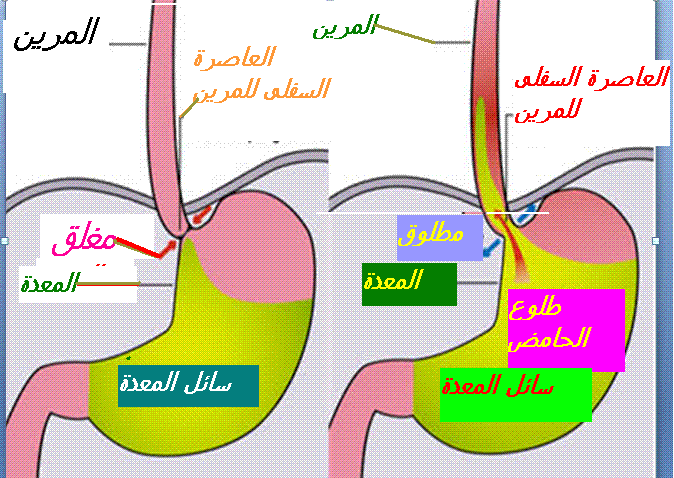

تحتل أدوية م م ب المحل الرئيسي في أخذ موقف علاج حالة الارتجاع المعدي المريئي. يبات ا م م أقل حموضة وبالتالي أقل تسمما للغشاء المخاطي المريني (13) الأمر الذي يؤول الى سرعة التئام الآفات أو جروح الالتهابات المريئية (14). بجانب تحقيق وتراجع الأعراض الناجمة عن الارتجاع المعدي المريئي يتم اللجوء الى تناول م م ب . بجانب تحقيق وتراجع اعراض الناجمة عن الارتجاعي المعدي المريئي. يتم اللجوء لتناول م م ب قصد التئام التهاب المريء الناجم عن حالة الترجيع المعدي المريئي للوقاية ضد الانتكاسات التي تبرز بعد التئام الجراح بجانب علاج حالة الجزر المعدي المريئي الذي تخلفه عقاقير ا م م البروتون التميز بالأعراض السريرية و وجود الدم في البراز. تختلف الجرعات الموصي بها حسب وجود أو عدم التهاب المريء. يلخص جدول رقم 1

. تتمثل الأعراض كأول خطوة السريرية في الحرقان، الارتجاع، السائل الحمضي في الفم) .و بدون الإصابة بالتهاب المريء . ما يتم اقتراح قواعد التغذية والنظافة (19) كأول خطوة بالنسبة للأشكال الأقل شدة. وفي حالة الإخفاق أو الأعراض الأكثر شدة يتم اقتراح أدوية م م ب مثل ما توصف مضادات الحمض الألجينية (20) يستخدم حمض الألجنيك، بشكل خاص في طب الأسنان وصناعة الغراء (21) ، أو مضادات ه2 (22) في حالة غياب انجاز الفحوص الإضافية حينما لا يعاني المصاب من علامة التخدير (23)(العمر أقل من 50 سنة و عدم نقص وزن الجسم بجانب عدم تدهور الحالة الصحية و عدم بروز علاقة النزيف الهضمي و عدم الإصابة بسوء البلع و عدم الإصابة بسوء البلع (24) .

يتحتم أن يتم التقييم 4 أسابيع من العلاج حينما يبرز المصاب أعراض سريرية بالرغم من تناول م م ب ، فيمسي اقتراح الفحوص الإضافية أمرا قائما. لتأكيد أو عدم تأكيد وجود حالة ا م ب والبحث عن سبب آخر الأعراض السريرية بالرغم من تناوله م م ب يمسي الاستمرار في متابعة العلاج بأدنى جرعة فعالة محتملة، يصبح أمرا قائما يطرح فوق طاولة المناقشة. و حينما تنتكس الأعراض النمطية بعد إيقاف العلاج، فينصح التالي باللجوء لإنجاز فحوص إضافية للتأكيد من وجود ا م م .